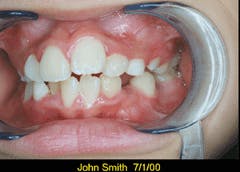

With Picture CD software included on the disk, you can add a patient`s name and the date taken to each image.

The software on the disk will enable you to view and modify the images, enhance color, rotate the images, and add a patient`s name and the date taken to each image. You can print the images in various sizes. You can even print several images to a single 81/2 x 11-inch sheet.